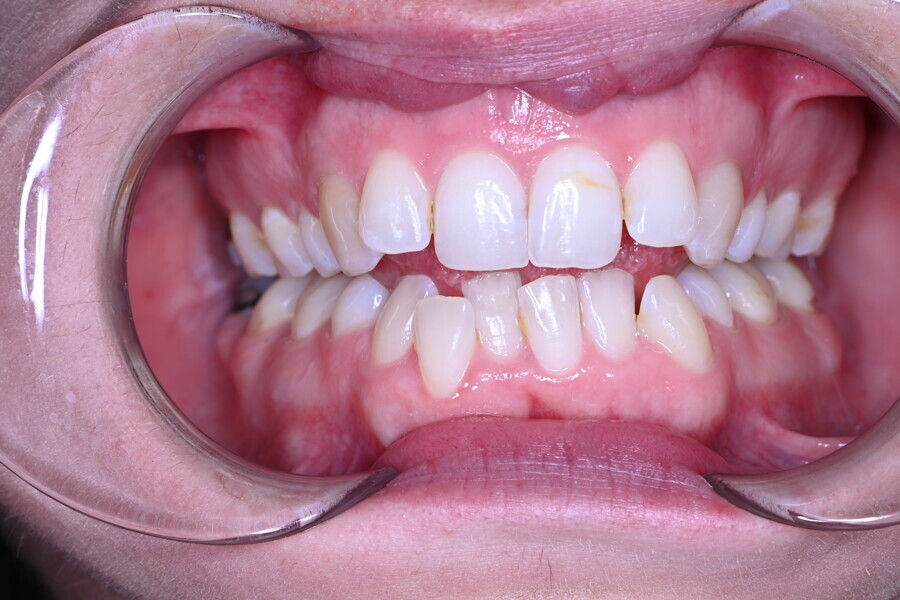

The 58-year-old patient wished to improve his oral aesthetics and function, complaining of mobility of the posterior teeth and wear of the anterior teeth. After data collection, a very complex situation was identified (Figs. 11–13):

1. severe periodontitis with poor prognosis of some teeth;

2. anterior crossbite;

3. severe wear mainly of the anterior teeth and compensatory eruption;38

4. atypical swallowing and lower posture of the tongue at rest;

5. masticatory dysfunction during the mastication test; and

6. no significant signs of temporomandibular disorder.